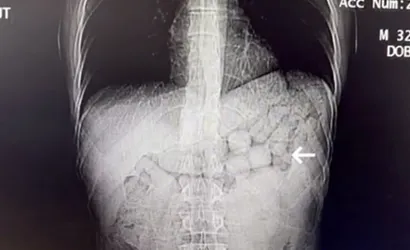

Çekilen tomografi görüntülerinde şüphelilerin mide ve bağırsak bölümlerinde yabancı cisimlere rastlandı.

Yaklaşık 3 gün süren tıbbi kontroller sonucunda şahıslardan 91 kapsül içinde toplam 807,15 gram Metamfetamin ele geçirildi. Şüpheliler gözaltına alındı ve emniyetteki işlemlerinin ardından sevk edildikleri adli makamlarca tutuklandı.